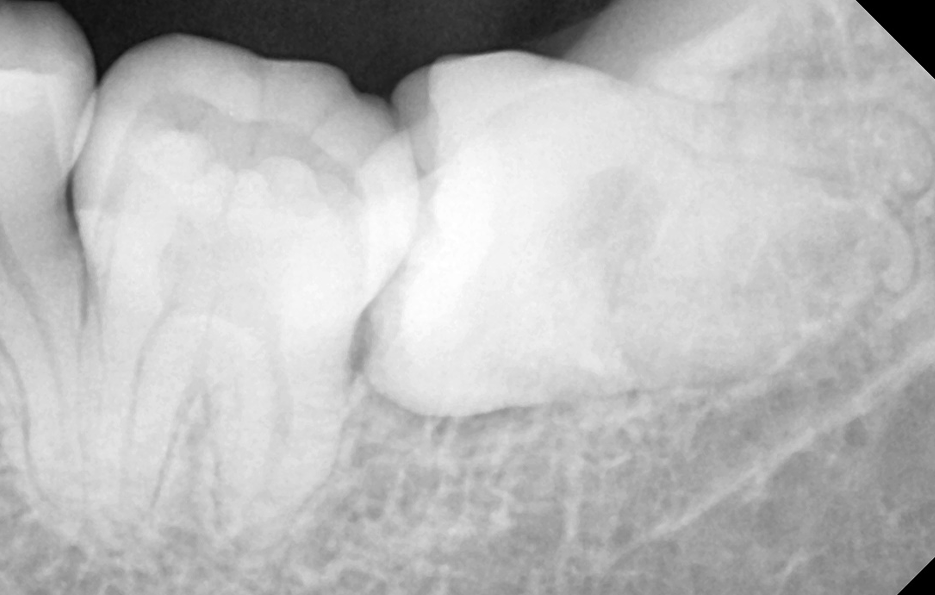

사랑니는 사람마다 다르게 생겼다고 알고는 계시겠지만 실질적으로 어떻게 생겼고 구분되는지 잘 모르시는 분들도 많을 거예요. 사랑니의 모양을 기준으로 형태를 나눠보면 똑바로 정상 맹출된 사랑니와 부분적으로 매복되어 있는 사랑니, 완전 매복되어 있는 모양으로 구분할 수 있는데요.

완전 매복되어 있는 사랑니 중에서는 어금니 쪽 방향으로 누워서 자라는 경우도 있고 어금니의 반대방향으로 누워 자라기도 하며 완전히 수평으로 매복되어 있기도 하고 수직으로 매복되어 있는 경우로도 또 다시 분류할 수 있어요.

동일한 조건이라고 가정할 때 사랑니의 모양에 따라 발치 난이도가 달라져요

사랑니 발치에 있어서 사랑니가 충치로 인해 썩었거나 현재 잇몸이 붓고 염증이 발생한 상황과 같이 특정 상황적 조건을 무시하고 사랑니의 모양만을 두고 발치 난이도를 구분해보자면 당연하게도 정상적으로 맹출된 사랑니가 보다 뽑기 쉽다고 할 수 있겠고 반면에 완전 매복되어 있는 사랑니의 경우 보다 발치의 어려움을 느낄 수 있는데요

위 환자분의 사랑니 케이스를 살펴보면 윗니의 경우 정상 맹출된 사랑니의 형태를 보이지만 아랫니의 경우에는 부분 매복되어 있고 누워서 자라고 있는 사랑니의 형태를 볼 수 있어요. 다 그런 것은 아니지만 윗니의 경우 중력에 의해 정상 맹출된 사랑니의 형태가 좀더 많다면 아랫니의 경우 매복사랑니의 형태가 많은 편이기 때문에 하악 사랑니의 발치가 좀더 어려운 경우가 있어요